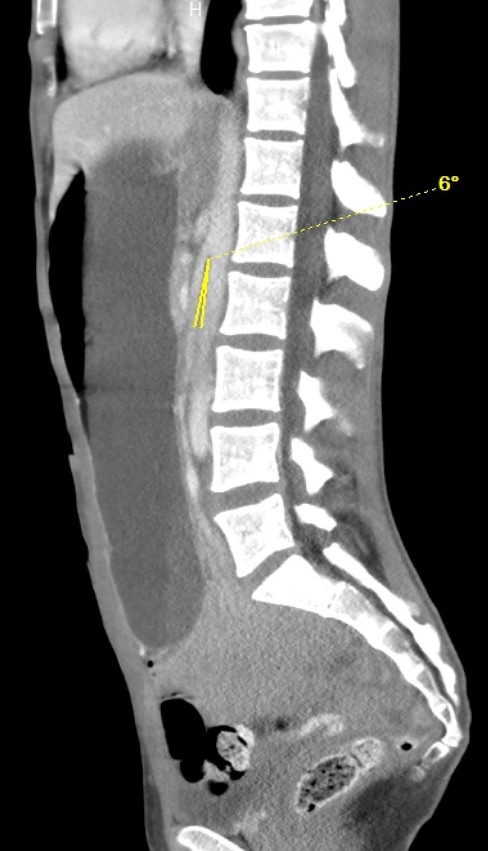

Introduction: Wilkie's Syndrome, also known as Superior Mesenteric Artery Syndrome (SMAS), is a rare cause of bowel obstruction that can contribute to vague abdominal symptoms on clinical presentation. This syndrome occurs when the aortomesenteric angle decreases, compressing the third portion of the duodenum between the aorta and the superior mesenteric artery. An acute decrease in the mesenteric fat pad cushion between these two blood vessels is the primary etiology, although other causes (e.g., anatomical, postoperative, functional, and pubescent etiologies) have also been described.

Case presentation: In the present cases, 2 females with a common history of recent weight loss presented to our institution with similar symptoms of abdominal pain, nausea and vomiting. Each patient was subsequently diagnosed with SMAS following imaging studies. Both patients experienced successful resolution of symptoms with conservative nutritional management.